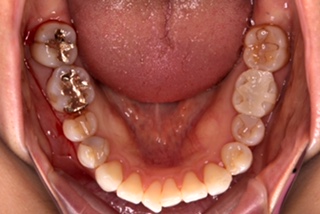

今回の治療は、右(この写真では左)の1番奥の金属、

奥から3番目はプラスチックが欠けてしまったので

セラミックにしてもらいました。

どうですか?

本来の歯と変わらないくらいに、綺麗に入れていただきました。

見た目もさる事ながらセラミックは強度が強く、表面がツルツルなので

汚れも付きにくく、金属と違い熱の影響なども受けにくい為

接着部の歪み生じにくく、外れたり、隙間から再び虫歯になるリスクを

下げれます。